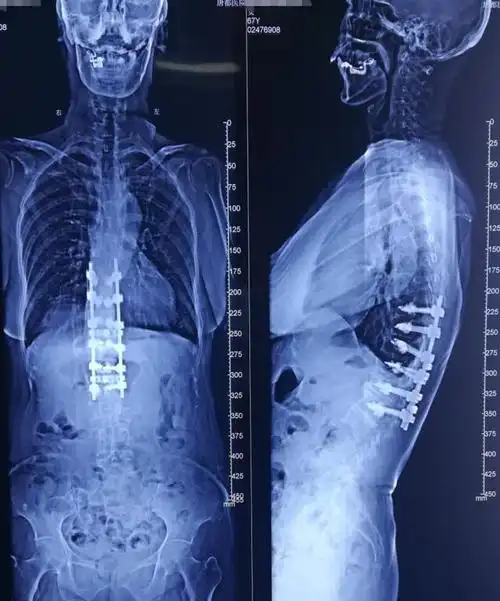

病例分享:脊柱后凸畸形矫形术

病例分享胸腰段脊柱后凸畸形

男子脊柱后凸 手术成功矫形,10多年来第一次躺下睡个踏实觉